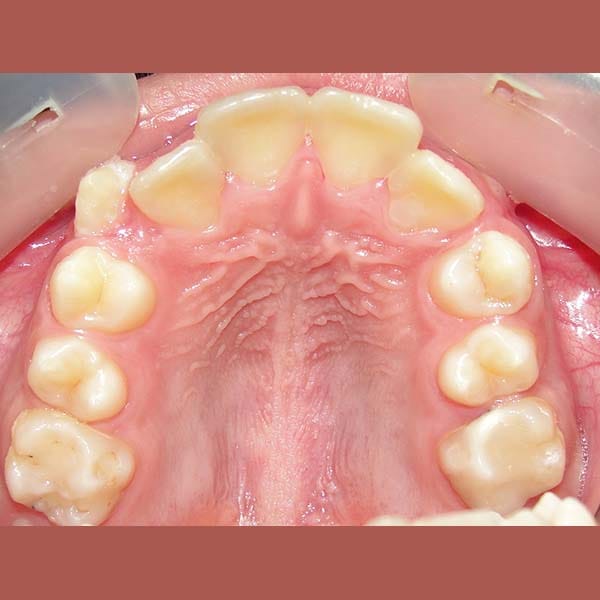

BEFORE

This young woman suffered from an upper jaw stenosis, crowded teeth, and the absence of one of the upper molars.

She was treated with Daimon braces (an orthodontic device that doesn’t require rubber to fix the archwires, which reduces friction and speeds up treatment).

At the end of the treatment, we were able to see a clear expansion in her upper jaw, her teeth were aligned beautifully, and the gap resulting from the absence of the molar was closed orthodontically.